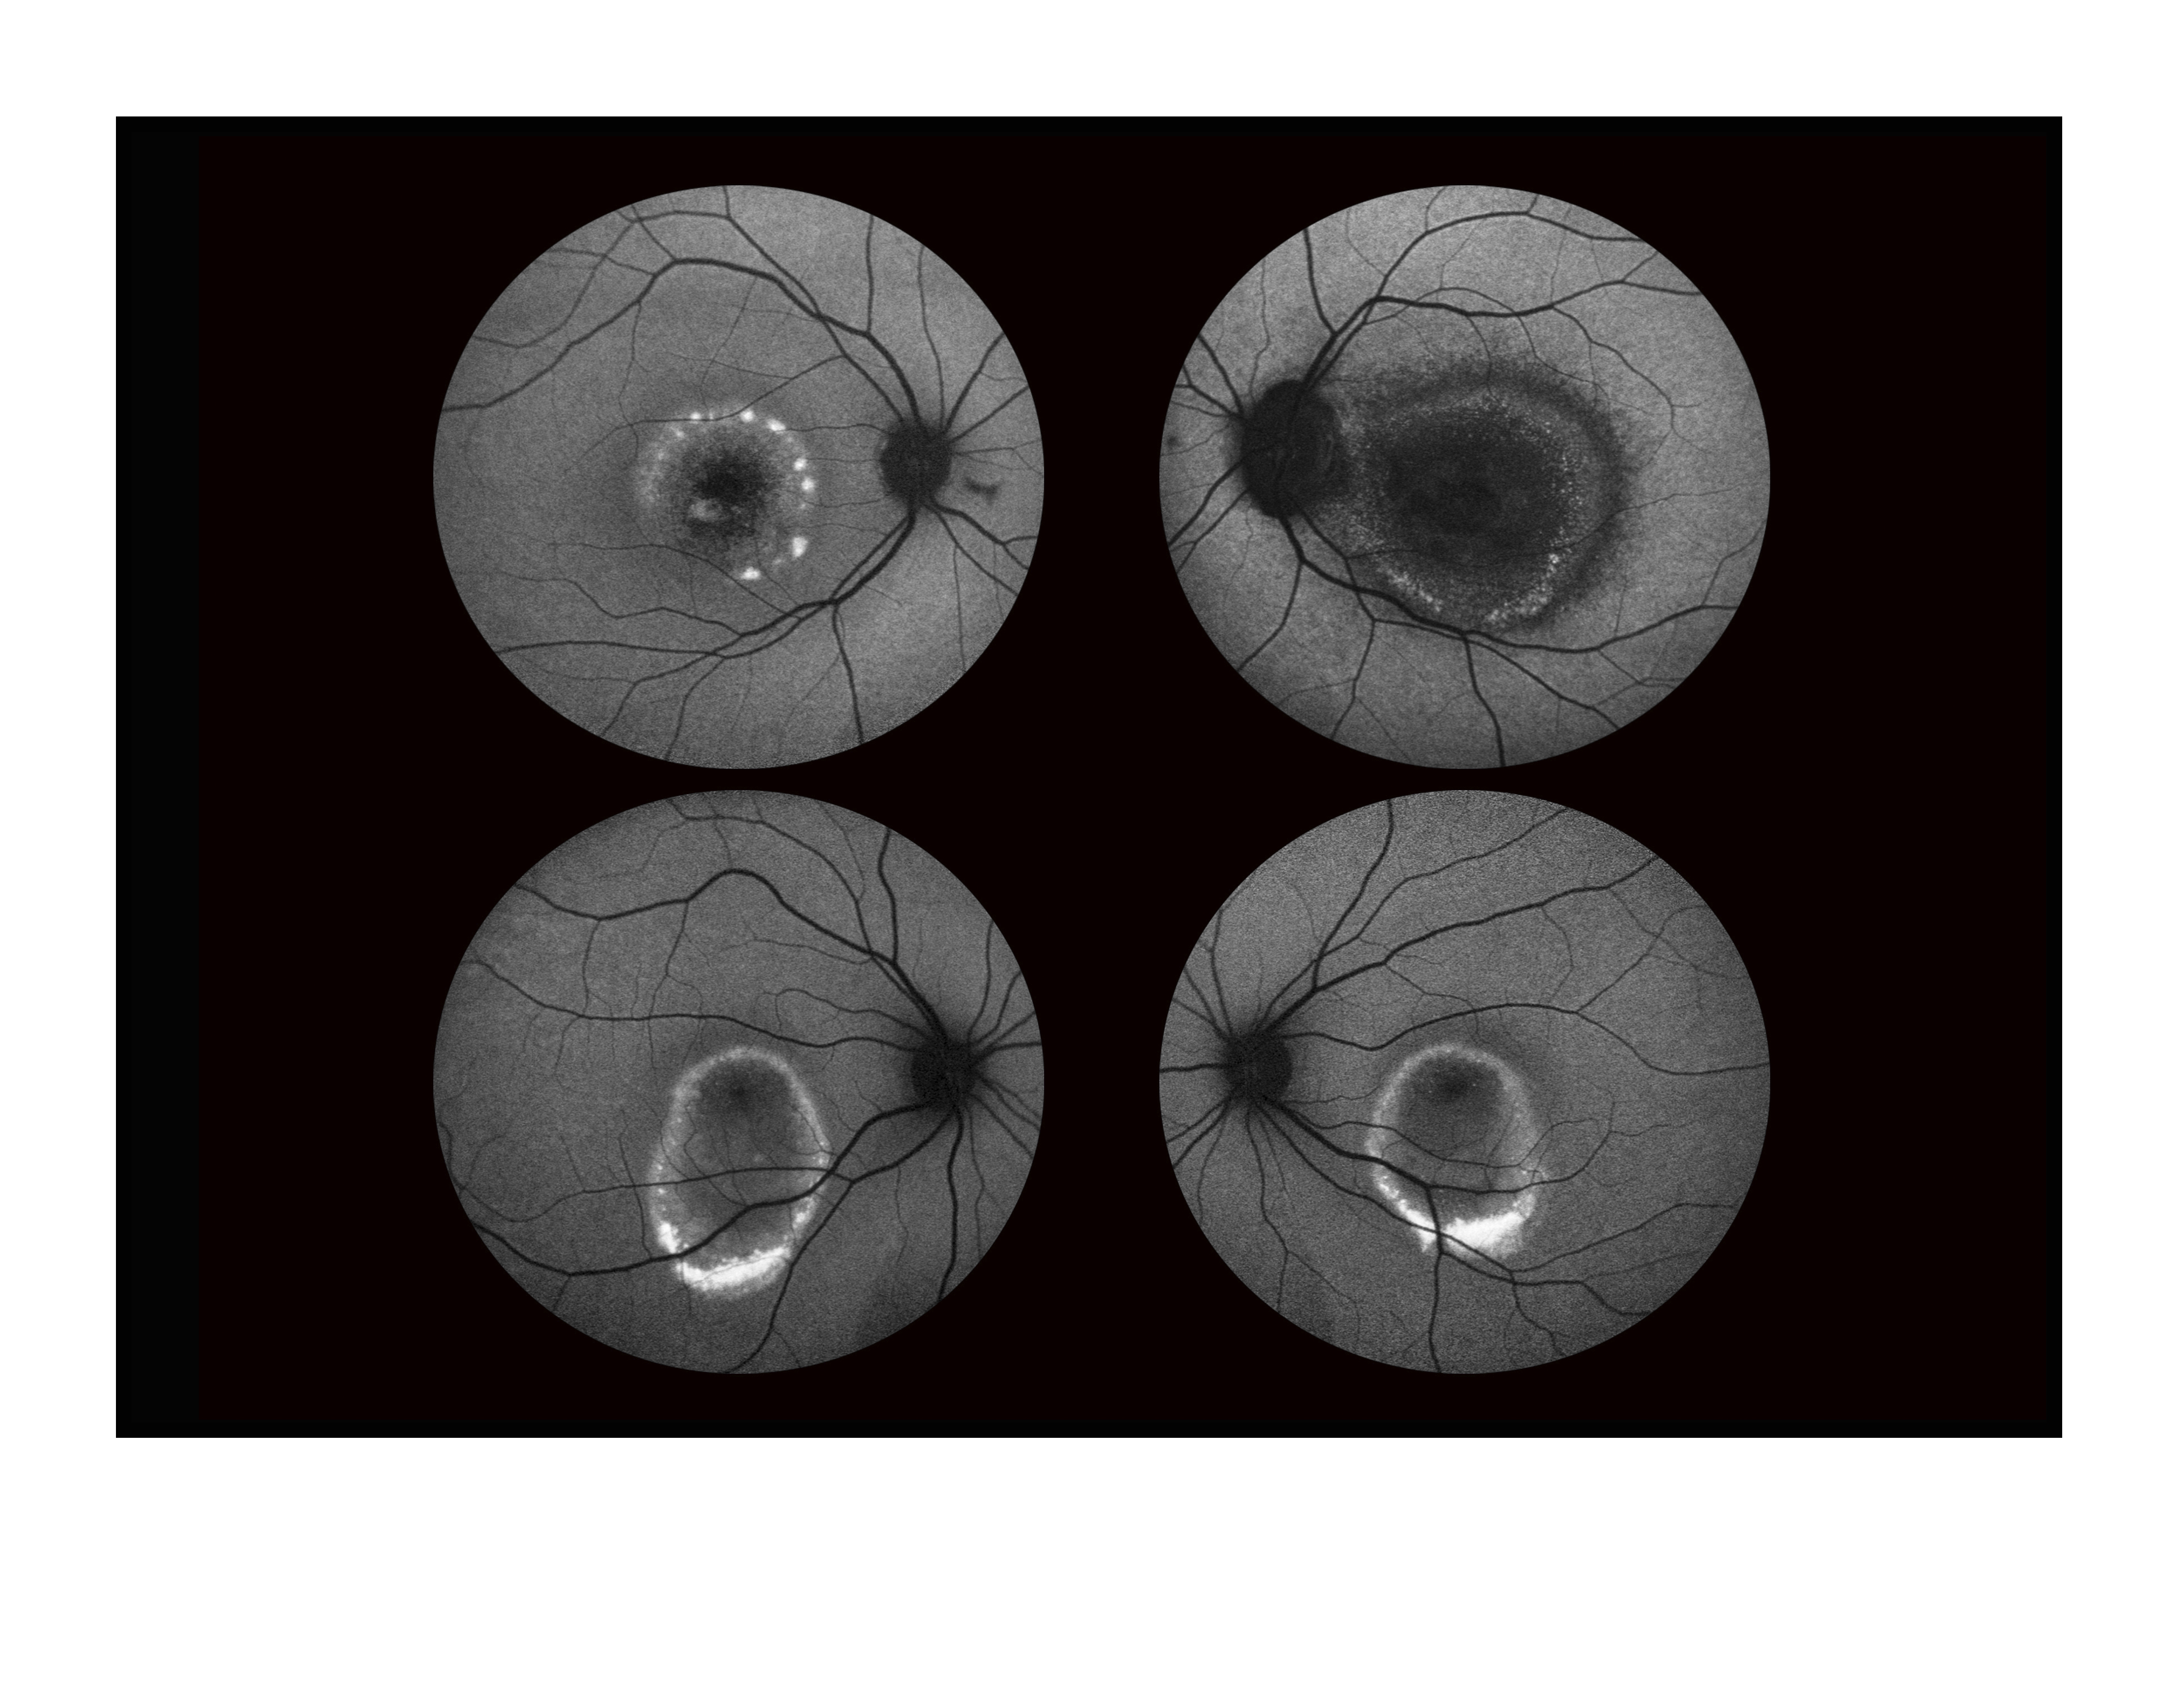

Father And Son With Best Dystrophy Presented by Mark Harrod, CRA, OCT-C This photograph received Second Place in the category "Fundus Autofluorescence" and was displayed in the 2024 OPS Exhibit. Filed Under Retina OPS Photo